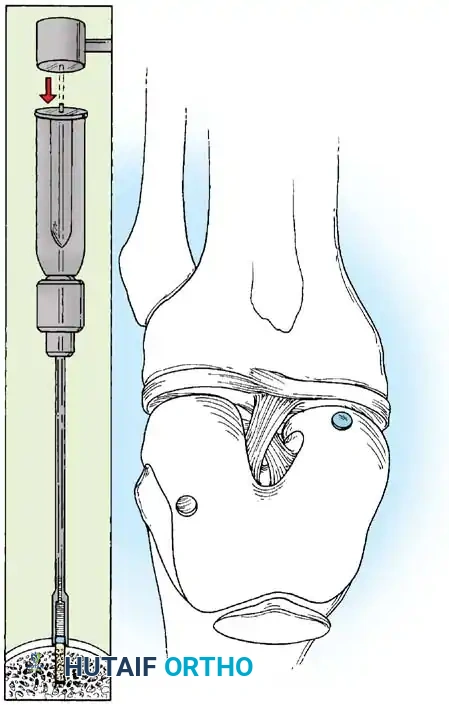

Classifi cation of Meniscal Tears Classifi cation of the types of meniscal tears encountered during diagnostic arthroscopy of the knee is essential in planning the subsequent arthroscopic resection or repair. Although numerous classifi cations of meniscal tears exist, the following, proposed by O’Connor, has proved useful. O’Connor classifi ed the patterns of meniscal tears into the following categories: (1) longitudinal tears; (2) horizontal tears; (3) oblique tears; (4) radial tears (Fig. 48-10); and (5) variations, which include fl ap tears, complex tears, and degenerative meniscal tears. Longitudinal tears most commonly occur as a result of trauma to a reasonably normal meniscus. The tear usually is vertically oriented and may extend completely through the thickness of the meniscus or may extend only partially or incompletely through it. The tear is oriented parallel to the edge of the meniscus, and if the tear is complete, a displaceable inner fragment frequently is produced. When the inner fragment displaces over into the intercondylar notch, it commonly is referred to as a bucket-handle tear (Fig. 48-11). If the tear is near the meniscocapsular attachment of the meniscus, it commonly is referred to as a peripheral

Fig. 48-12 Zone classifi cation of meniscus (modifi ed from Cooper et al.). Most anterior zone of medial meniscus is labeled C, whereas most anterior zone of lateral meniscus is labeled D . 0 is meniscosynovial junction; I is outer third, II is middle third, and III is inner third of each meniscus. (Redrawn from Newman AP, Daniels AU, Burks RT: Principles and decision making in meniscal surgery, Arthroscopy 9:33, 1993.) tear. A peripheral vertical tear in zone I, referred to as a red-red tear, and a tear between zone I and II, referred to as a red-white tear, are in the vascularized portion of the meniscus (Fig. 48-12). These peripheral tears should be repaired when feasible. Horizontal tears tend to be more common in older patients, with the horizontal cleavage plane occurring from shear, which divides the superior and inferior surfaces of the meniscus (see Fig. 48-9B). These are more commonly seen in the posterior half of the medial meniscus or the midsegment of the lateral meniscus. Many fl ap tears and complex tears begin with a horizontal cleavage component.

Oblique tears are full-thickness tears running obliquely from the inner edge of the meniscus out into the body of the meniscus. If the base of the tear is posterior, it is referred to as a posterior oblique tear (see Fig. 48-9C); the base of an anterior oblique tear is in the anterior horn of the meniscus (Fig. 48-13). Radial tears, similar to oblique tears, are vertically oriented, extending from the inner edge of the meniscus toward its periphery, and can be complete or incomplete (see Fig. 48-9D), depending on the extent of involvement. These probably are similar in pathogenesis to oblique tears (Fig. 48-14). The possible variations include fl ap tears, complex tears, and degenerative meniscal tears. Flap tears are similar to oblique tears, but usually have a horizontal cleavage element, rather than being purely vertical in orientation. Tears containing a horizontal element often are referred to as superior or inferior fl ap tears, depending on where the fl ap is based on the surface of the meniscus. Complex tears may contain elements of all of the abovementioned types of tears and are more common in chronic meniscal lesions or in older degenerative menisci. These generally are caused by chronic, long-standing, altered mechanics of the meniscus, and the initial tear occurring in the meniscus may not be identifi able after several different planes of tearing have resulted. Degenerative tears often refer to complex tears. These present with marked irregularity and complex tearing within the meniscus (see Fig. 48-9E and F). These are most often seen in older patients.